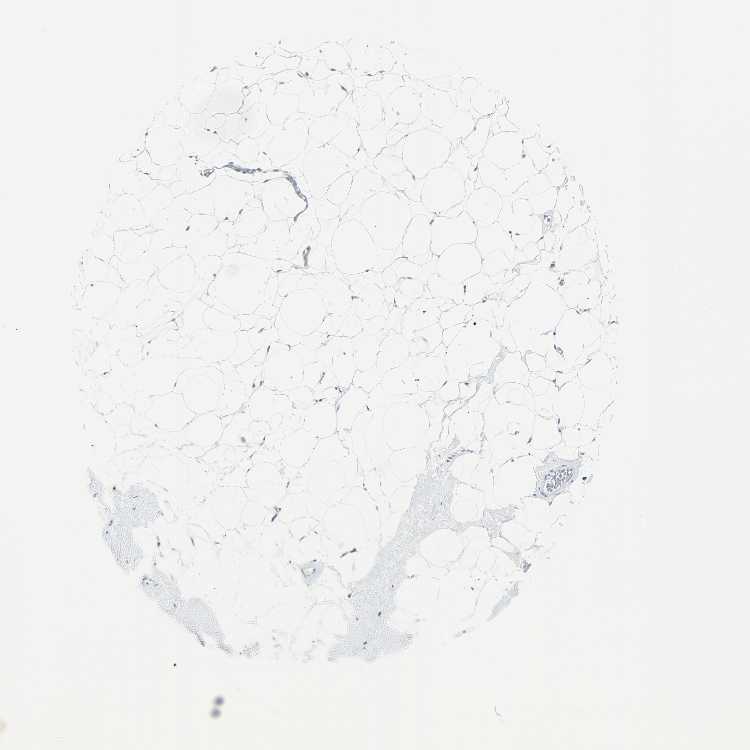

BREAST - Antibody stainingi

Antibody staining in the annotated cell types in the current human tissue is reported as not detected, low, medium, or high, based on conventional immunohistochemistry profiling in selected tissues. This score is based on the combination of the staining intensity and fraction of stained cells.

Each image is clickable and will lead to virtual microscopy that enables deeper exploration of all samples and also displays staining intensity scores, fraction scores and subcellular localization as well as patient and tissue information for each sample.

Antibody HPA007401

Adipocytes Not detected